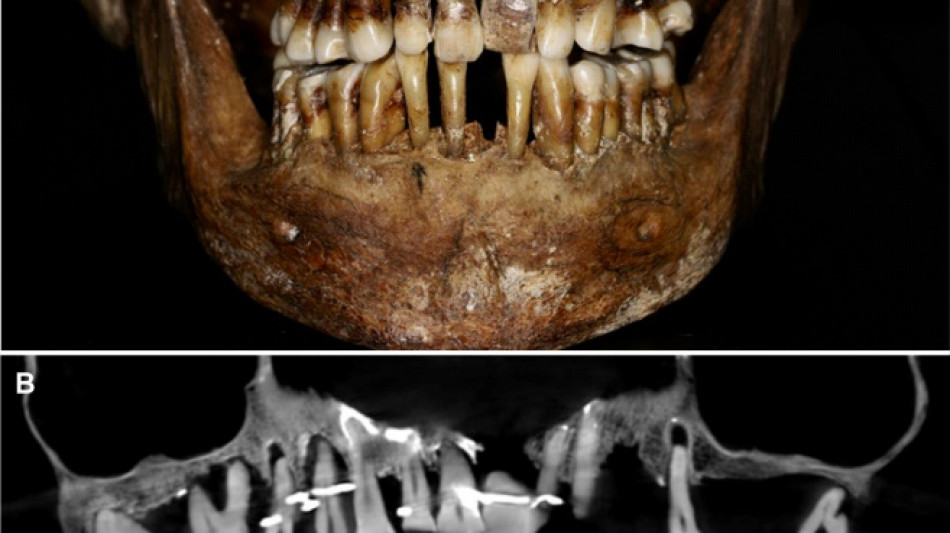

Scientists have discovered the long-buried secret of a 17th-century French aristocrat 400 years after her death: she was using gold wire to keep her teeth from falling out.

Embalmed in a lead coffin, her skeleton -- and teeth -- were remarkably well preserved.

At the time the archaeologists noticed that she had a dental prosthetic, but they did not have advanced scanning tools to find out more.

Thirty-five years later, a team of archaeologists and dentists have identified that d'Alegre suffered from periodontal disease that was loosening her teeth, according to a study published in the Journal of Archaeological Science: Reports this week.

A "Cone Beam" scan, which uses X-rays to build three-dimensional images, showed that gold wire had been used to hold together and tighten several of her teeth.

She also had an artificial tooth made of ivory from an elephant -- not hippopotamus, which was popular at the time.

The gold wires would have needed repeated tightening over the years, further destabilising the neighbouring teeth, the researchers said.